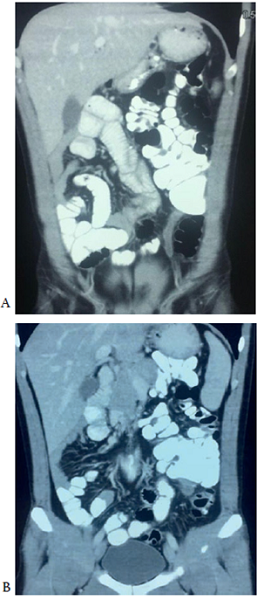

En los exámenes de laboratorio se encontró leucocitosis (21.500/mm3), neutrofilia (86 %) y proteína C reactiva de 16,3 mg/L. La ecografía total de abdomen estuvo dentro de parámetros normales. En la tomografía computadorizada de abdomen (figura 1 y figura 2) se observó que el bulbo y la segunda porción del duodeno tenían un recorrido habitual, pero la tercera y la cuarta porción no cruzaban la línea media, identificándose asas intestinales delgadas (yeyuno e íleon) en el hemiabdomen derecho. La válvula ileocecal se encontraba en la fosa ilíaca izquierda, y el apéndice cecal estaba aumentado de tamaño e hipodenso, sin captación del medio de contraste, con un diámetro aproximado de 7,3 mm en la punta, 7,5 en la base y 7,2 en el tercio medio. Por lo anterior, se consideró el diagnóstico de rotación intestinal anormal, con válvula ileocecal en la fosa iliaca izquierda y apendicitis aguda izquierda.